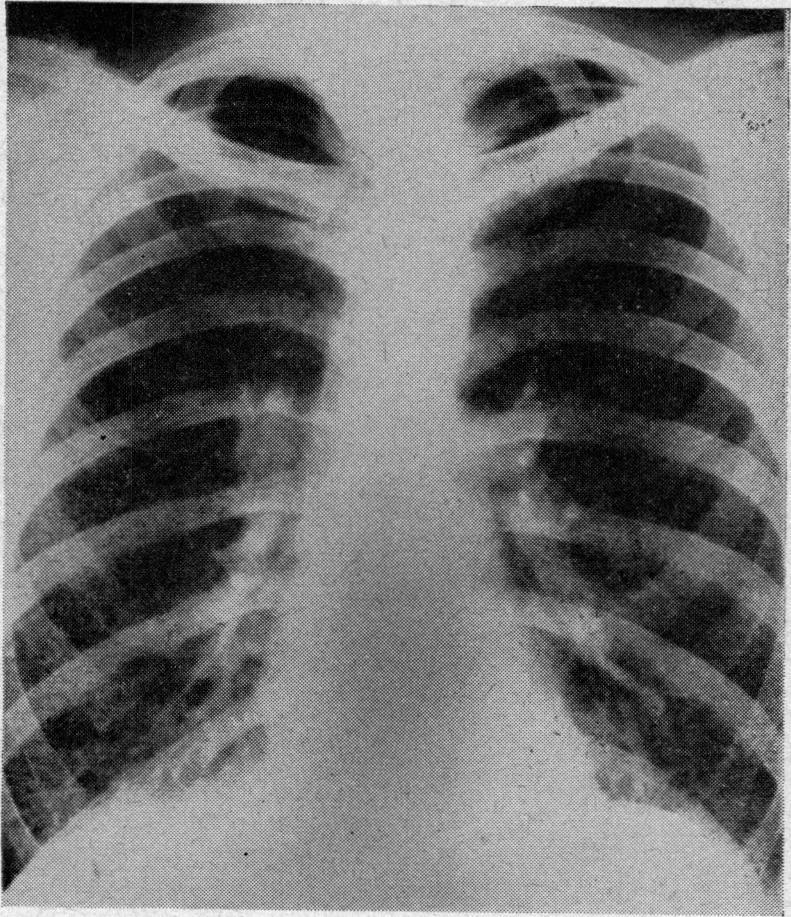

KARLISH A J

Proc R Soc Med. 1962 Mar;55(3):223-5. doi: 10.1177/003591576205500310.